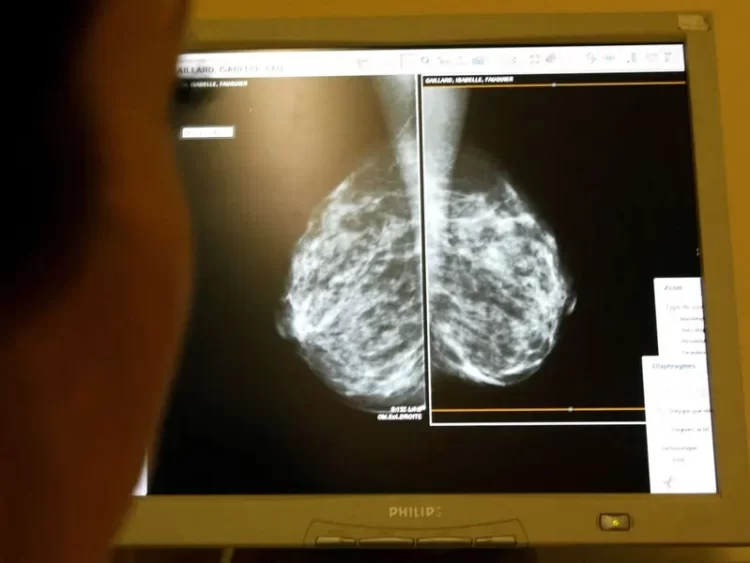

FDA aprueba nuevo tratamiento contra el cáncer de mama en etapas tempranas

La decisión de la agencia reguladora se fundamenta en los resultados obtenidos en el ensayo clínico, aplicado a mujeres con cáncer de mama inicial

La Administración de Alimentos y Medicamentos de Estados Unidos (FDA) otorgó el martes la aprobación al uso de ribociclib adyuvante (Kisqali) en combinación con un inhibidor de la aromatasa, destinado a pacientes adultas con cáncer de mama en etapa temprana, específicamente en los estados II y III. Este tratamiento está indicado para aquellos con receptor hormonal positivo (HR) y HER2 negativo, que presentan un alto riesgo de recurrencia.